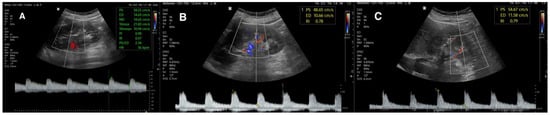

3.2. Renal Flow Parameters

3.2.1. Renal Resistive Index

3.2.2. Peak Systolic Velocity and Renal–Aortic Ratio

3.2.3. Acceleration Time and Acceleration Index